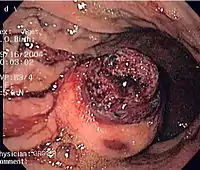

CT scanning is often undertaken (see the radiology section).

The definitive diagnosis is made with a biopsy, which can be obtained endoscopically, percutaneously with CT or ultrasound guidance or at the time of surgery. A biopsy sample will be investigated under the microscope by a pathologist physician. The pathologist examines the histopathology to identify the characteristics of GISTs (spindle cells in 70-80%, epitheloid aspect in 20-30%). Smaller tumors can usually be confined to the muscularis propria layer of the intestinal wall. Large ones grow, mainly outward, from the bowel wall until the point where they outstrip their blood supply and necrose (die) on the inside, forming a cavity that may eventually come to communicate with the bowel lumen.

When GIST is suspected—as opposed to other causes for similar tumors—the pathologist can use immunohistochemistry (specific antibodies that stain the molecule CD117 [also known as c-kit] —see below). 95% of all GISTs are CD117-positive (other possible markers include CD34, DOG-1, desmin, and vimentin). Other cells that show CD117 positivity are mast cells.

If the CD117 stain is negative and suspicion remains that the tumor is a GIST, the newer antibody DOG-1 (Discovered On GIST-1) can be used. Also sequencing of Kit and PDGFRA can be used to prove the diagnosis.

Imaging

The purpose of radiologic imaging is to locate the lesion, evaluate for signs of invasion and detect metastasis. Features of GIST vary depending on tumor size and organ of origin. The diameter can range from a few millimeters to more than 30 cm. Larger tumors usually cause symptoms in contrast to those found incidentally which tend to be smaller and have better prognosis.[4][13] Large tumors tend to exhibit malignant behavior but small GISTs may also demonstrate clinically aggressive behavior.[14]

Small GISTs

Since GISTs arise from the bowel layer called muscularis propria (which is deeper to the mucosa and submucosa from a luminal perspective), small GIST imaging usually suggest a submucosal process or a mass within the bowel wall. In barium swallow studies, these GISTs most commonly present with smooth borders forming right or obtuse angles with the nearby bowel wall, as seen with any other intramural mass. The mucosal surface is usually intact except for areas of ulceration, which are generally present in 50% of GISTs. Ulcerations fill with barium causing a bull's eye or target lesion appearance. In contrast-enhanced CT, small GISTs are seen as smooth, sharply defined intramural masses with homogeneous attenuation.